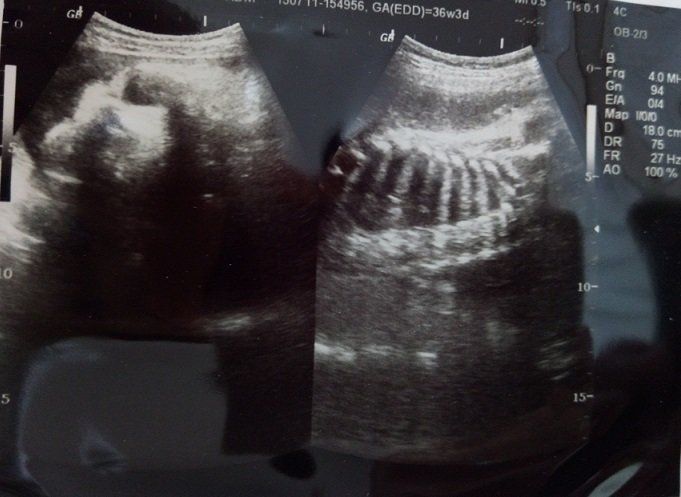

妊娠36週のエコー写真 存在感あるなあ!出産へのカウントダウン始まる

臨月に入って、いよいよ毎週の通院になりました。赤ちゃんが出産に向けて元気であるかどうか調べるNST(ノンストレステスト)も始まり、出産へのカウントダウンが始まりました。